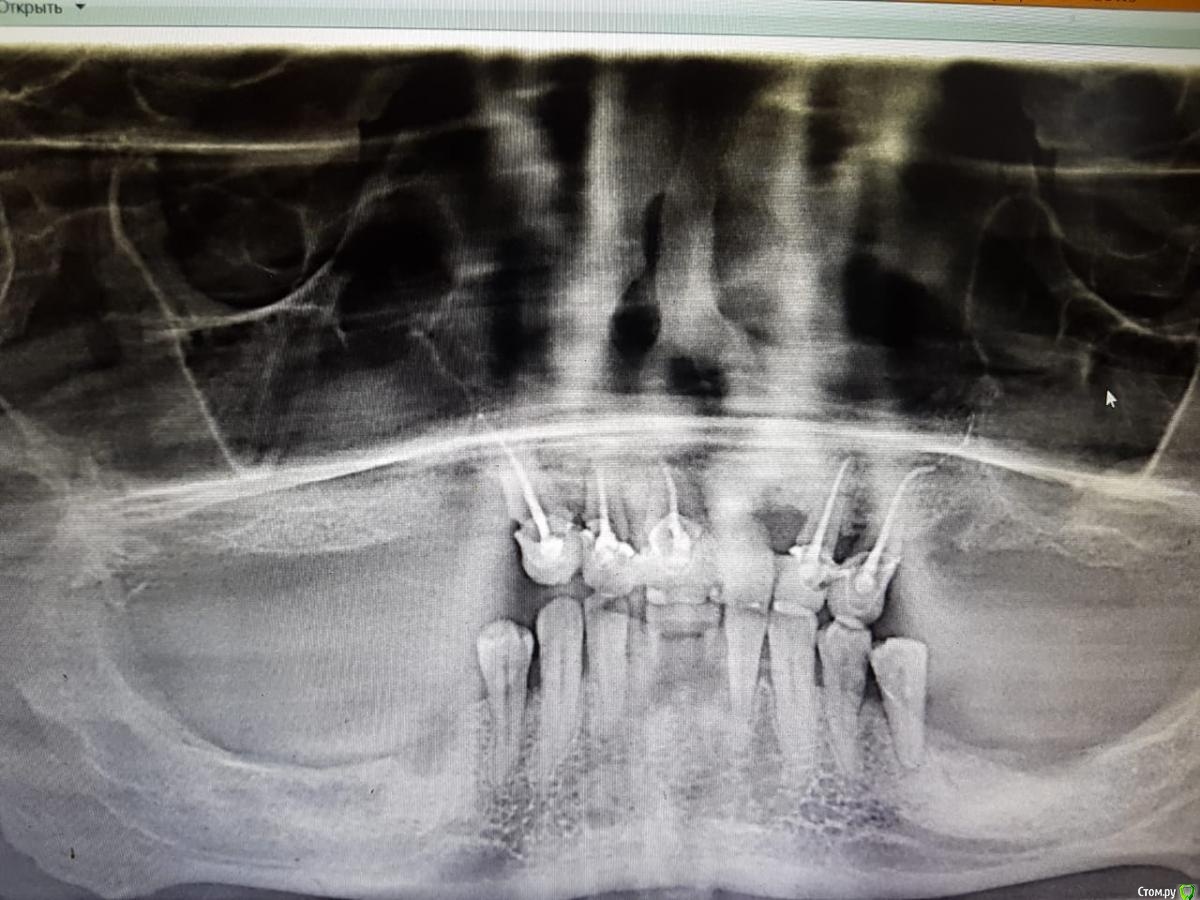

kosa1 Опубликовано 30 сентября, 2020 Поделиться Опубликовано 30 сентября, 2020 (изменено) Пришел пациент, делаем мост. протез. У терапевта при лечении зуба 1.3 гипохлоран из шприца выплеснулся (сорвалась игла) и попал в полость рта, глаза, в нос.3 дня из полости носа вытекала жидкость, потом прекратилась. На следующий день под глазом появилась припухлость, увеличивалась в размерах. Носогубная складка сгладилась, выраженный отек, при пальпации боль, пальпируется шарообразное образование. После приема антибиотиков (5 дней амоксиклав 625 ) отек практически спал и боль прошла, но через 2 дня отек сново начал увеличиваться. Оптг спустя 2 недели. Изменено 30 сентября, 2020 пользователем kosa1 Ссылка на комментарий